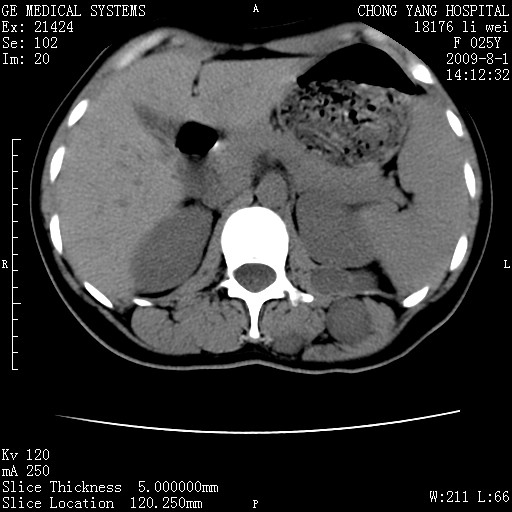

以下是引用pujunzhi在2009-8-1 20:23:00的发言:[br]胸椎旁及背部肌间良性病变,范围广,边界清,沿肌间生长,考虑淋巴管瘤、血管瘤,建议增强扫描。